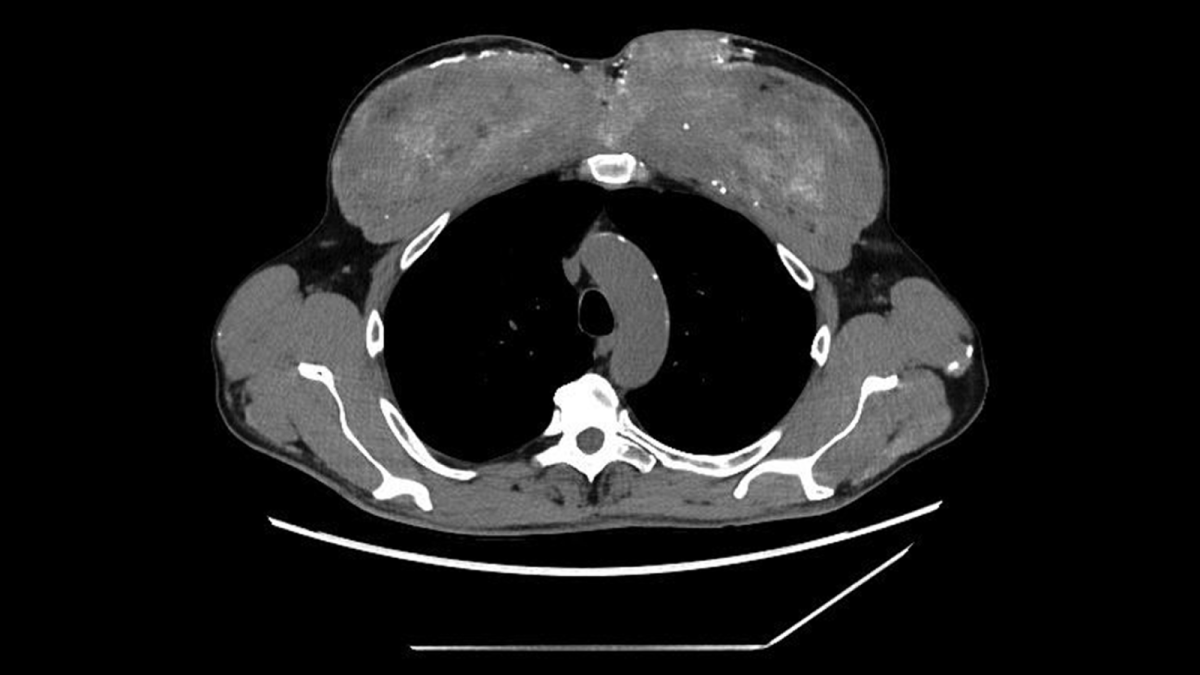

قرر الفريق الطبي إجراء فحوصات تصوير مقطعي، ليتضح أن التكلّسات لا تقتصر على الدم فقط؛ فقد كانت منتشرة في الكليتين والبنكرياس والمعدة، كما ظهرت بقع تشبه الندبات في الرئتين. غير أن أكثر ما أثار الريبة كان التغيّر الغريب في عضلات الصدر، التي بدت متكلّسة بشكل كثيف وغير طبيعي.

تم إدخال الرجل للعلاج، فحصل على مدرّات البول، والسوائل الوريدية، والستيرويدات، وأدوية لخفض الكالسيوم. انخفضت مستويات الكالسيوم مؤقتاً، لكنه وبعد أسابيع قليلة عاد إلى المستشفى بمشكلة أكبر وهي أن الكالسيوم يرتفع من جديد دون أي سبب واضح. عند إعادة الفحص، لُوحظ أن عضلات الذراعين والصدر مشوهة وغير طبيعية، تماماً مثلما ظهر في صور الأشعة.